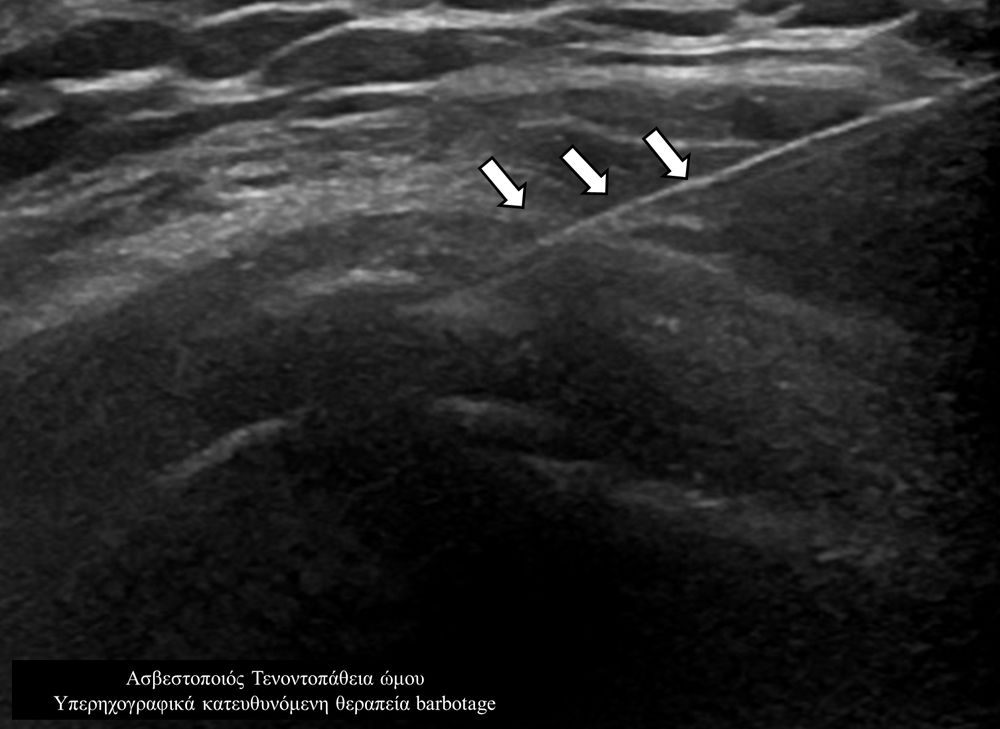

Η υπερηχογραφικά καθοδηγούμενη αφαίρεση των επασβεστώσεων (barbotage) είναι μια ελάχιστα παρεμβατική (minimally invasive) τεχνική θεραπείας για την ασβεστοποιό τενοντοπάθεια. Με τους υπερήχους είναι δυνατός ο εντοπισμός των ασβεστώσεων και η διαδερμική τοποθέτηση μιας βελόνας στο κέντρο της συμπτωματικής ασβέστωσης. Στη συνέχεια γίνεται διαδερμικός τρυπανισμός και επαναλαμβανόμενες πλύσεις του ασβεστίου, με αποτέλεσμα τόσο την αφαίρεση της παθολογικής επασβέστωσης όσο και την αυξηση τοπικά της αιμάτωσης με αποτελεσμα την σταδιακή απομάκρυνση των παραγόντων φλεγμονής-ερεθισμού.